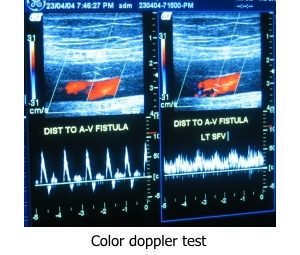

Color Doppler/Ultrasound of vein: Color Doppler test helps in the diagnosis of varicose veins, deep vein thrombosis (DVT).

Color Doppler/Ultrasound of peripheral arteries: This is a basic test to confirm arterial blood supply to the peripheral organs like upper and lower limbs.

Dialysis access evaluation ultrasound: This ultrasound helps in evaluating the diameter and condition of veins of upper limb which are commonly used for dialysis access fistula.

Color Doppler/Ultrasound of vein: Color Doppler test helps in the diagnosis of varicose veins, deep vein thrombosis (DVT).

Color Doppler/Ultrasound of peripheral arteries: This is a basic test to confirm arterial blood supply to the peripheral organs like upper and lower limbs.

Dialysis access evaluation ultrasound: This ultrasound helps in evaluating the diameter and condition of veins of upper limb which are commonly used for dialysis access fistula.